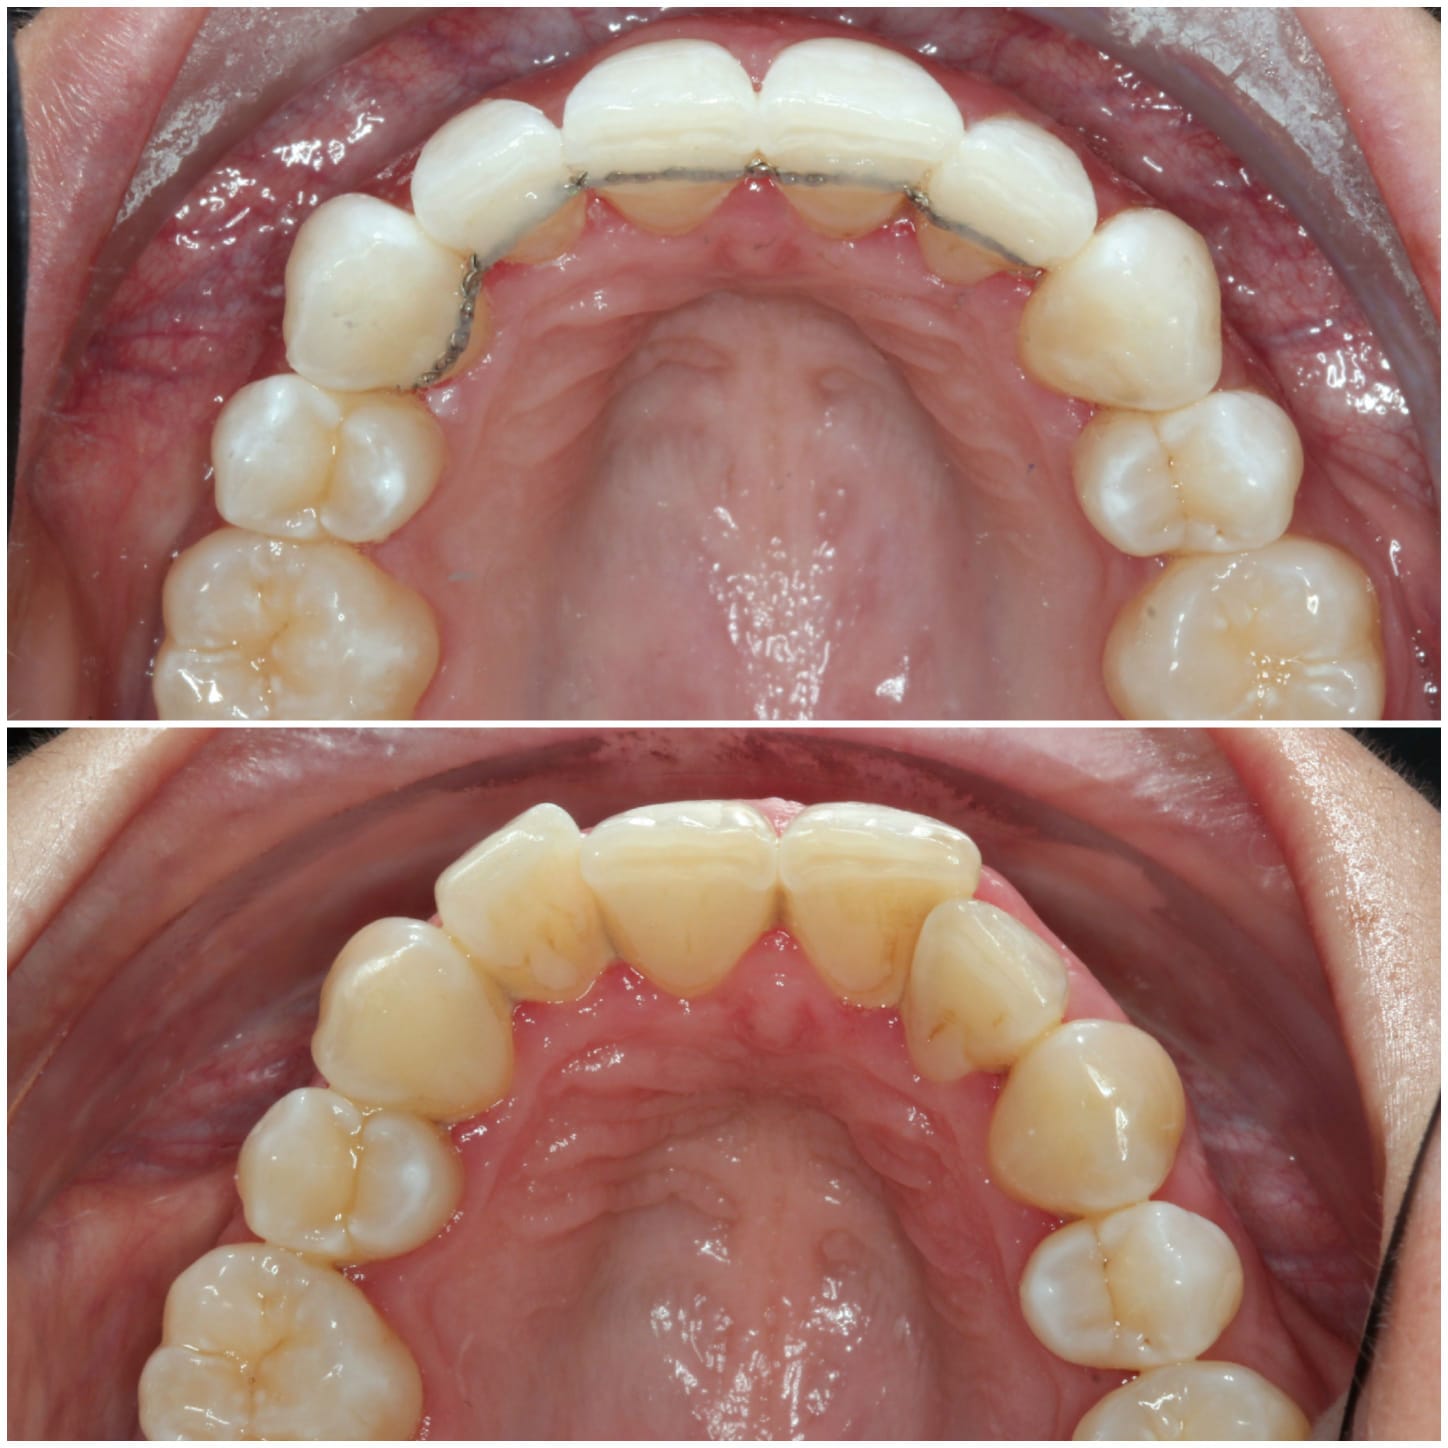

Invisalign is a clear alternative to traditional metal braces, offering a discreet and convenient way to achieve a straighter smile. Unlike traditional braces, Invisalign aligners are removable and nearly invisible, allowing you to eat, drink, and live your life without restriction. With Invisalign, you can straighten your teeth without the hassle and self-consciousness of metal braces.

Invisalign is a well-known system for straightening teeth in the most discreet way. It works by using a series of clear aligners that fit comfortably over the teeth to gently move them into the desired position over time. There are no fixed brackets or wires used, in fact, the aligners are completely removable.